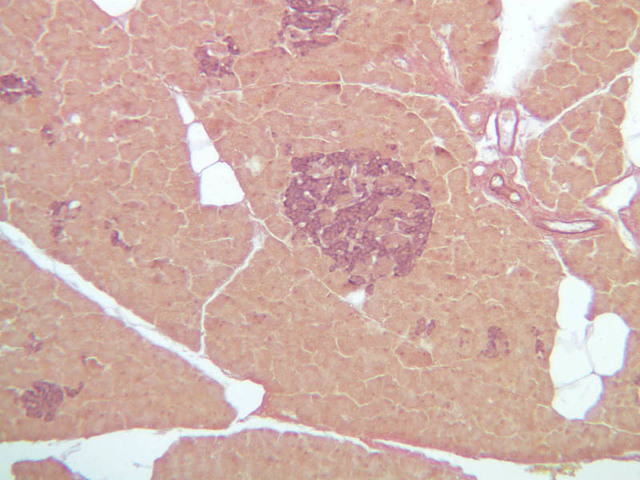

Although H & E staining permits ready identification of the islets of Langerhans, it does not permit differentiation of the various cell types that comprise the islets (B-36, H&E [10x, 20x, 40x-labeled]). There are no slides in the class collection that permit identification of all of the cell types of the endocrine pancreas. However, the sections on slides B-37 and B-40 permit specific identification of two cell types. Slide B-37 has been stained by the aldehyde fuchsin technique, which lends a magenta coloration to the granules of the insulin-producing B-cells. All other cells in the islets stain a dirty orange color (B-37 [10x, 20x, 40x] [10x, 20x, 40x]). Most of these orange-colored cells are the glucagon-secreting A-cells; however, you should bear in mind that somatostatin-secreting D-cells, as well as APUD cells that secrete pancreatic polypeptide are also scattered about the islet. The section on slide B-40 has been prepared by a silver impregnation method that renders some of the APUD cells in the islets (which appear as “clear cells” in ordinary preparations) dark brown or black (B-40 [10x, 20x, 40x]).

The specimen on slide B-39 was prepared by perfusing India ink into the blood stream of an animal. Examine this specimen with an eye to understanding how the capillary beds of the exocrine and endocrine portions of the pancreas differ (B-39, Ink/H&E [10x, 20x-labeled] [10x] [10x, 20x]).